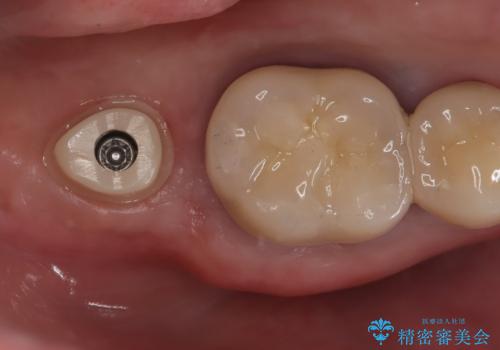

インプラントを入れるためには十分な骨の高さと幅が必要です。術前に検査を行い必要であれば別途、骨や角化歯肉を増やす治療も行う事があります。

インプラントの土台と被せ物は適合が良い物を制作するため、シリコン印象材を使用し型を取っています。